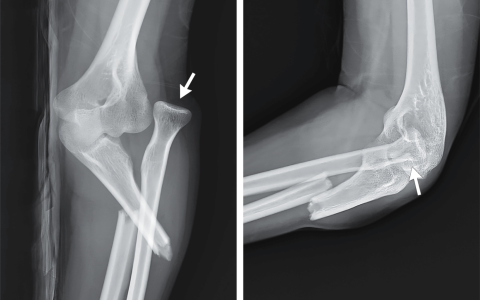

A 26-year-old woman presented with pain in her left elbow after falling on an outstretched hand while ice-skating. Physical examination revealed left lateral elbow swelling and tenderness to palpation, a valgus deformity, and limited range of motion. Which of the following findings are present on the imaging?一名26岁女性在滑冰时摔倒,手掌撑地,随后出现左肘疼痛。体格检查显示左肘外侧肿胀、触痛、外翻畸形以及活动范围受限。以下哪项影像学表现是存在的?

这是一类被称为 Monteggia 骨折脱位 的损伤,其特征是 尺骨近端骨折 合并 肱桡关节脱位。这种骨折通常发生在人摔倒时手掌撑地,前臂处于 极度旋前 位的情况下。早期识别并进行手术干预对于预防 长期功能障碍、桡神经损伤或肘关节僵硬 至关重要。

正确答案:B